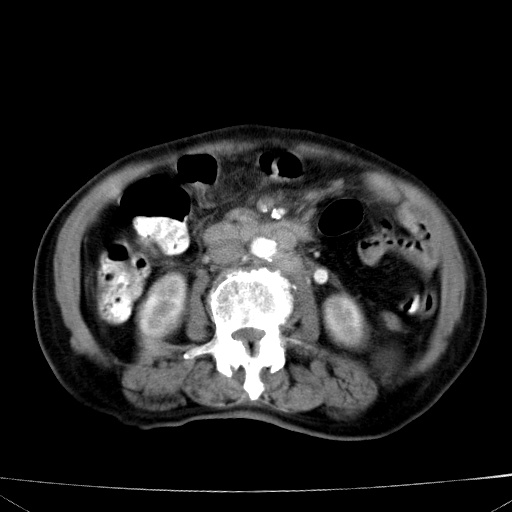

网站人气太旺!昨天的帖子就沉到海底,只好再发贴!ct18338:女 78岁,肝胆病变,已增强,再会诊!原帖链接:http://www.radida.com/bbs/forum.php?mod=viewthread&tid=50032

1)考虑胆囊癌侵犯肝脏并肝门区、腹膜后及右侧膈角后淋巴结转移。2)肝左叶近肝顶部囊肿。3)肝左叶肝内胆管结石。4)左肾近下极囊肿。

1)考虑胆囊癌侵犯肝脏并肝门区、腹膜后及右侧膈角后淋巴结转移。2)肝左叶近肝顶部囊肿。3)肝左叶肝内胆管结石。4)左肾近下极囊肿。支持